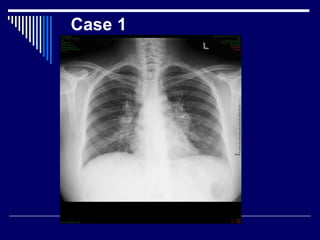

Case 1

Findings with marks

CXR of adult female

Bilateral symmetrical bulky hila (3)

 lungs = N (1)

CP angles = N (1)

Dx = Sarcoidosis ( stage 1) (3)

DD = lymphoma (1)

What next = CT chest (1)

Findings with marks CXRof adult female Bilateral symmetrical bulky hila (3)  lungs = N (1) CP angles = N (1) Dx = Sarcoidosis ( stage 1) (3) DD = lymphoma (1) What next = CT chest (1)